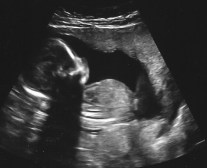

Mödravården i Sverige erbjuder idag flera ultraljud under graviditeten. Dessa används för att bland annat kunna se hur långt gången modern är, hur fostret utvecklas, hur mycket fostervatten finns och om fostret har några avvikelser.

Ett speciellt ultrajud, KUB och NUPP, görs mellan vecka 11 och 14. Detta ultraljud visar sannolikhet för olika typer av kromosomavvikelser, där vissa är allvarligare än andra. Testet går inte att göra tidigare än vecka 11 i graviditeten – ett ultraljud kan då inte visa om fostret har dessa avvikelser. Om testet görs i vecka 13 eller 14, skulle det enligt Sverigedemokraternas förslag innebära att Socialstyrelsens abortnämnd fattar beslut åt kvinnan baserat på resultatet av testet. Modern, eller föräldrarna, får alltså inte bestämma själva.

Först i vecka 14 kan ett ultraljud visa barnets kön, vilket gör det möjligt att ifrågasätta Paula Bielers uttalande om könssorterade aborter på svenska abortkliniker. Tidiga ultraljud erbjuds av flera kliniker med inriktning på mödravård, men eftersom det inte finns något medicinskt intresse att få veta könet tittar man inte på detta i regel vid tidiga ultraljud.